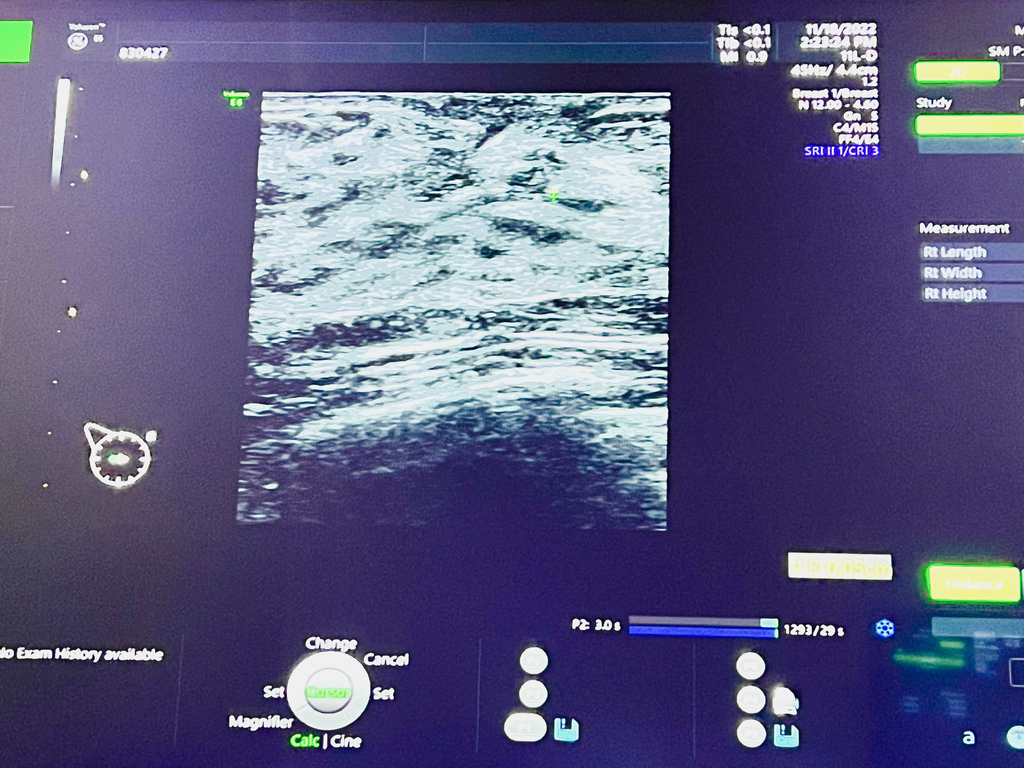

高層次乳房超音波是使用高頻率的音波來查看組織的波動,各年齡層都適合使用

再搭配4D精密高畫質儀器,以多種角度操作探頭,來檢測乳房是否有異狀

對於腫瘤、腺瘤、跟囊腫等病灶,也能找出具體的位子、形狀、及大小

這是一種非侵入性、無放射性的精密檢查

開始檢查時,健檢師會擠上一些凝膠與探頭在乳房按壓的方式來照超音波

再利用不同的角度檢查每個位置的狀況,同時也會細心介紹乳房內的組織

躺在床上,眼前有螢幕是會投射影像,方便健檢師在講解時

我們也可以清楚了解自身的乳房狀況